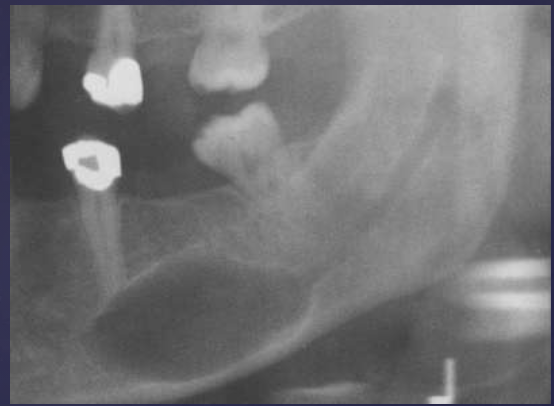

describe the ameloblastoma in this radiograph

multilocular w/ coarse septae

thinning of inferior mand border

displacement of teeth + IAN